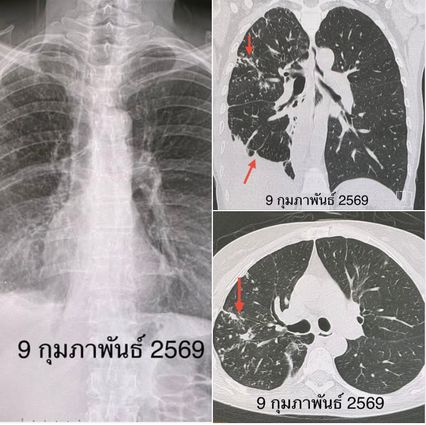

เอกซเรย์ปอด มีฝ้ากระจายในปอดข้างขวา มีน้ำเล็กน้อยในช่องเยื่อหุ้มปอดข้างขวา ทำเอกซเรย์คอมพิวเตอร์ปอด เห็นจุดกระจายในปอดข้างขวา หลอดลมโป่งพองในปอดข้างขวากลีบกลาง เห็นน้ำเล็กน้อยในเยื่อหุ้มปอดข้างขวา เนื่องจากผู้ป่วยขากเสมหะไม่ออก จึงส่องกล้องเข้าไปในหลอดลม เห็นเสมหะสีน้ำตาลในหลอดลมของปอดข้างขวา ย้อมเสมหะพบเชื้อ AFB ส่งตรวจสารพันธุกรรมพบเชื้อวัณโรค เพาะเชื้อขึ้นเชื้อวัณโรค กำลังรอผลตรวจความไวของเชื้อวัณโรคต่อยา